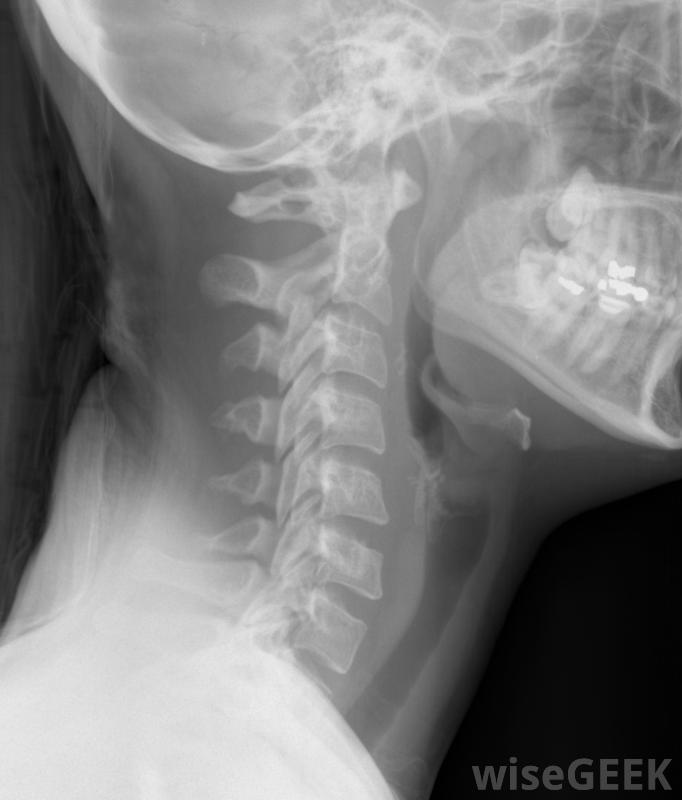

颈部的X光片,包括脊椎骨脊椎指压师接受的是人体生理学和生物学方面的普通教育,但他们的主要关注点是脊柱。脊椎指压师认为,脊椎和颈部的脊椎骨通常会因日常压力而偏离方向,这些错位(称为半脱位)可能是导致各种生理和心理疾病的根本原因,脊椎指压师希望通过对单个椎骨进行物理操作或调整整个脊柱来缓解半脱位造成的压力